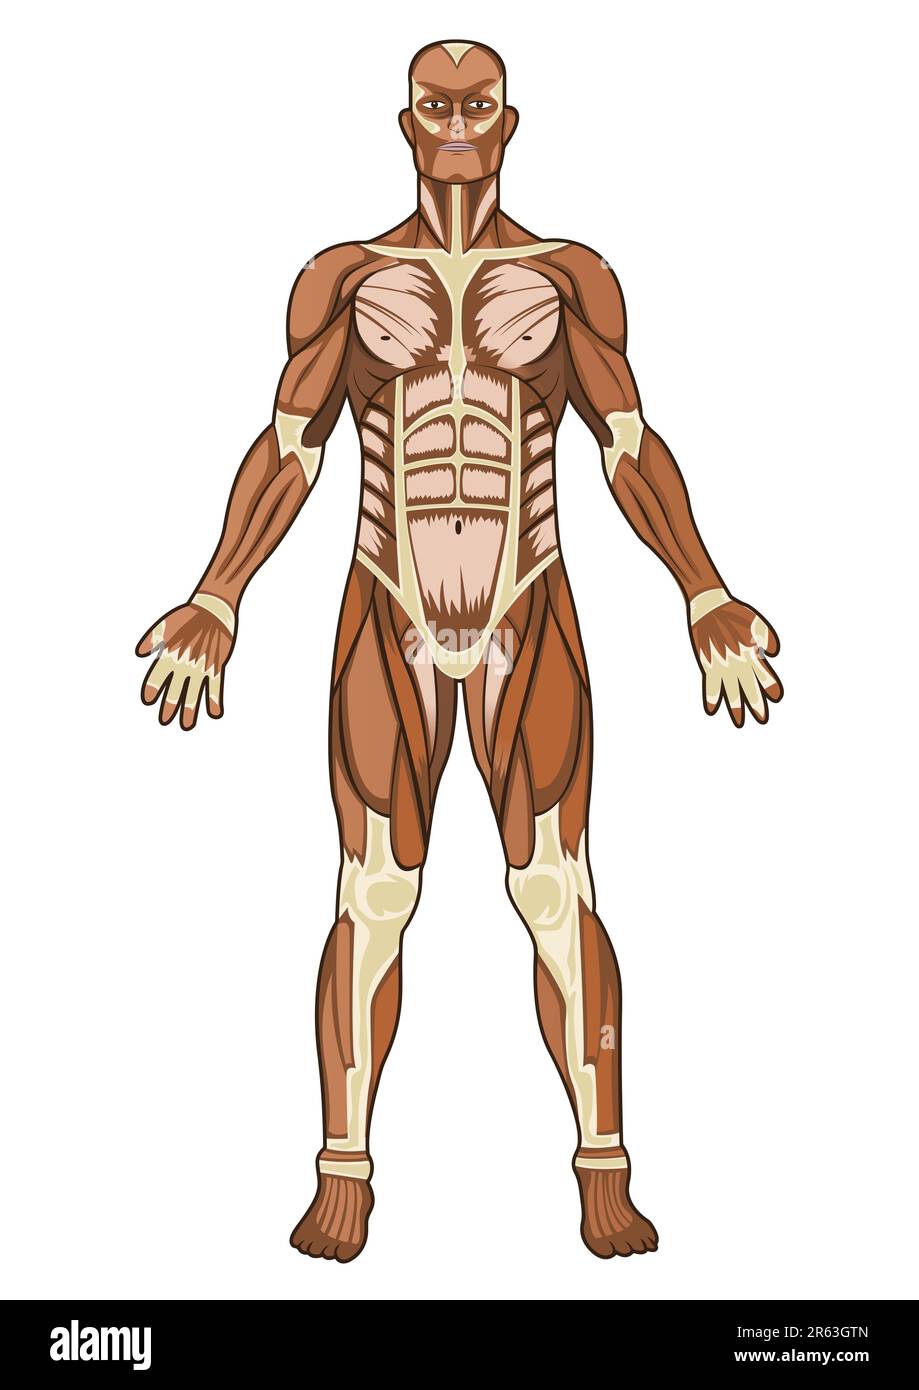

Human anatomy medical concept illustration in vector Stock Vectorhttps://www.alamy.com/image-license-details/?v=1https://www.alamy.com/human-anatomy-medical-concept-illustration-in-vector-image554498805.html

Human anatomy medical concept illustration in vector Stock Vectorhttps://www.alamy.com/image-license-details/?v=1https://www.alamy.com/human-anatomy-medical-concept-illustration-in-vector-image554498805.htmlRF2R63GTN–Human anatomy medical concept illustration in vector